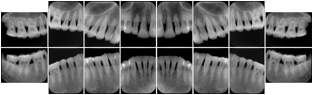

6 Standard + 4 Bitewing C Dental Image Layout

DL-P002E

Reference:

01

Standard

11, 12, 21, 22

11

32, 31, 41, 42

20

Bitewing

18, 17, 16, 15, 48, 47, 46, 45

21

17, 16, 15, 14 47, 46, 45, 44

23

27, 26, 25, 24, 37, 36, 35, 34

24

28, 27, 26, 25, 38, 37, 36, 35